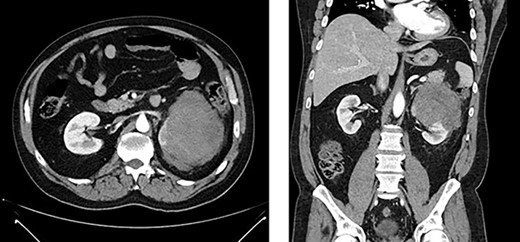

First appearance of multiple liver lesions suspicious for metastasis in transverse (left) and coronal (right) planes on CT; reduction of retroperitoneal effusion can also be seen.

Serial CT scans at 10 and 12 weeks post-resection revealed reduction of the retroperitoneal abscess and appearance of liver lesions concerning for metastasis (Fig. 4). The patient eventually completed his radiation course with no additional problems.